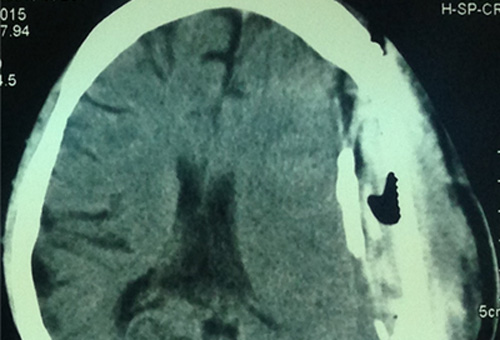

Trên thế giới các bác sĩ từng phát hiện răng mọc trong khối u não của bé trai4 tháng tuổi.

Theo đó, năm 2014, các bác sĩ tại trung tâm y tế Đại học Maryland (Mỹ) đã giải phẫu lấy khối u có răng trong não một bé trai 4 tháng tuổi.

Bệnh nhi có triệu chứng là đầu tăng trưởng nhanh hơn bình thường và những xét nghiệm sau đó cho thấy cháu bé có khối u sọ hầu (craniopharyngioma) - một dạng u hiếm gặp có thể phát triển to hơn quả bóng đánh golf.

Bé trai hiện trong tình trạng sức khỏe tốt sau khi được phẫu thuật. Bác sĩ ngoại thần kinh Narlin Beaty giải thích rằng, các nhà khoa học từng biết dạng khối u này được hình thành từ các tế bào liên quan tới việc mọc răng nhưng cho đến nay chưa ai phát hiện răng trong khối u sọ hầu.